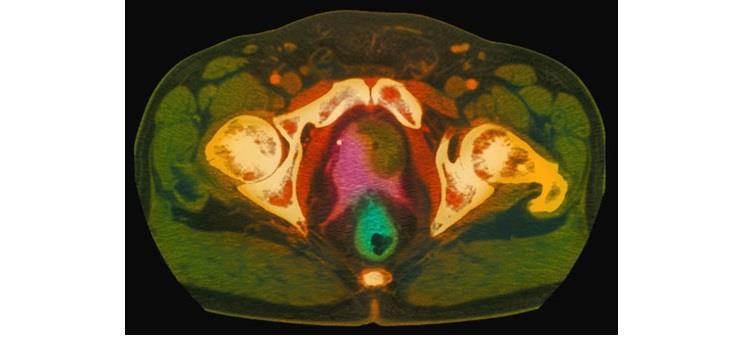

6- حالات الورم ومكانه

يظهر الورم في التصوير بالرنين المغناطيسي (في الصورة) ككتلة خضراء بجوار البروستاتا وردية اللون، ويكون السرطان إما صغيرا أو متقدما داخل البروستاتا، أو منتشرا خارجها أو في الأنسجة المجاورة مثل الحويصلات المنوية أو المثانة أو المستقيم، أو في العقد الليمفاوية أو العظام والرئتين.